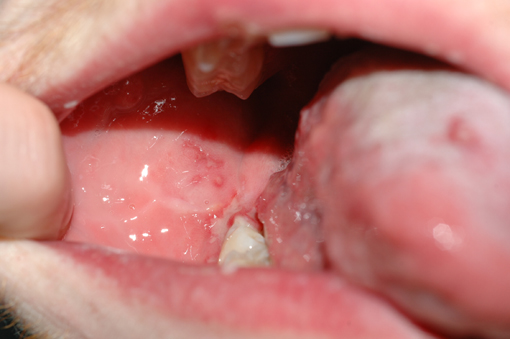

Vesiculo-bullous lesions (blisters)

These are technically slightly different lesions from ulcers. Ulcers are lesions of the mucous membrane, small (vesicles) and large (bullae) blisters are lesions of the epithelium (made up by superficial cells of the thin surface lining tissue). Blisters can either interrupt the adhesion between epithelial cells (intraepithelial blisters) or detach the epithelial layer from its underlying tissue (subepithelial blisters). These intraepithelial and subepithelial blisters / lesions are by and large oral manifestations of a number of different underlying diseases (see below), with the important exception of the spontaneous formation of oral blood blisters of unknown cause (angina bullosa haemorrhagica, these are irritating but benign in nature).